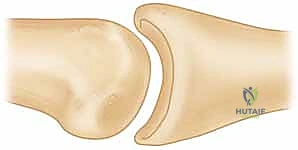

* FIG 4 • Unstable PIP palmar lip fracture-dislocation. Extensive damage has occurred to the palmar lip of the middle phalanx, but the dorsal cortical margin and a small amount of dorsal articular cartilage remain intact. Even slight dorsal subluxation can be detected by looking for a V-shaped gap between the middle and proximal phalanges.

*

* FIG 4 • Unstable PIP palmar lip fracture-dislocation (continued). Note the "V" sign indicating persistent dorsal subluxation.